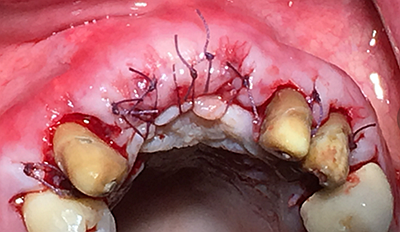

這時(shí)候縫合可能還會(huì)存在一些軟組織張力,這時(shí)候最好的辦法不是唇側(cè)減張縫合,看我的方法,既可以達(dá)到減張的目的又可以保證牙槽嵴頂角化齦充足。